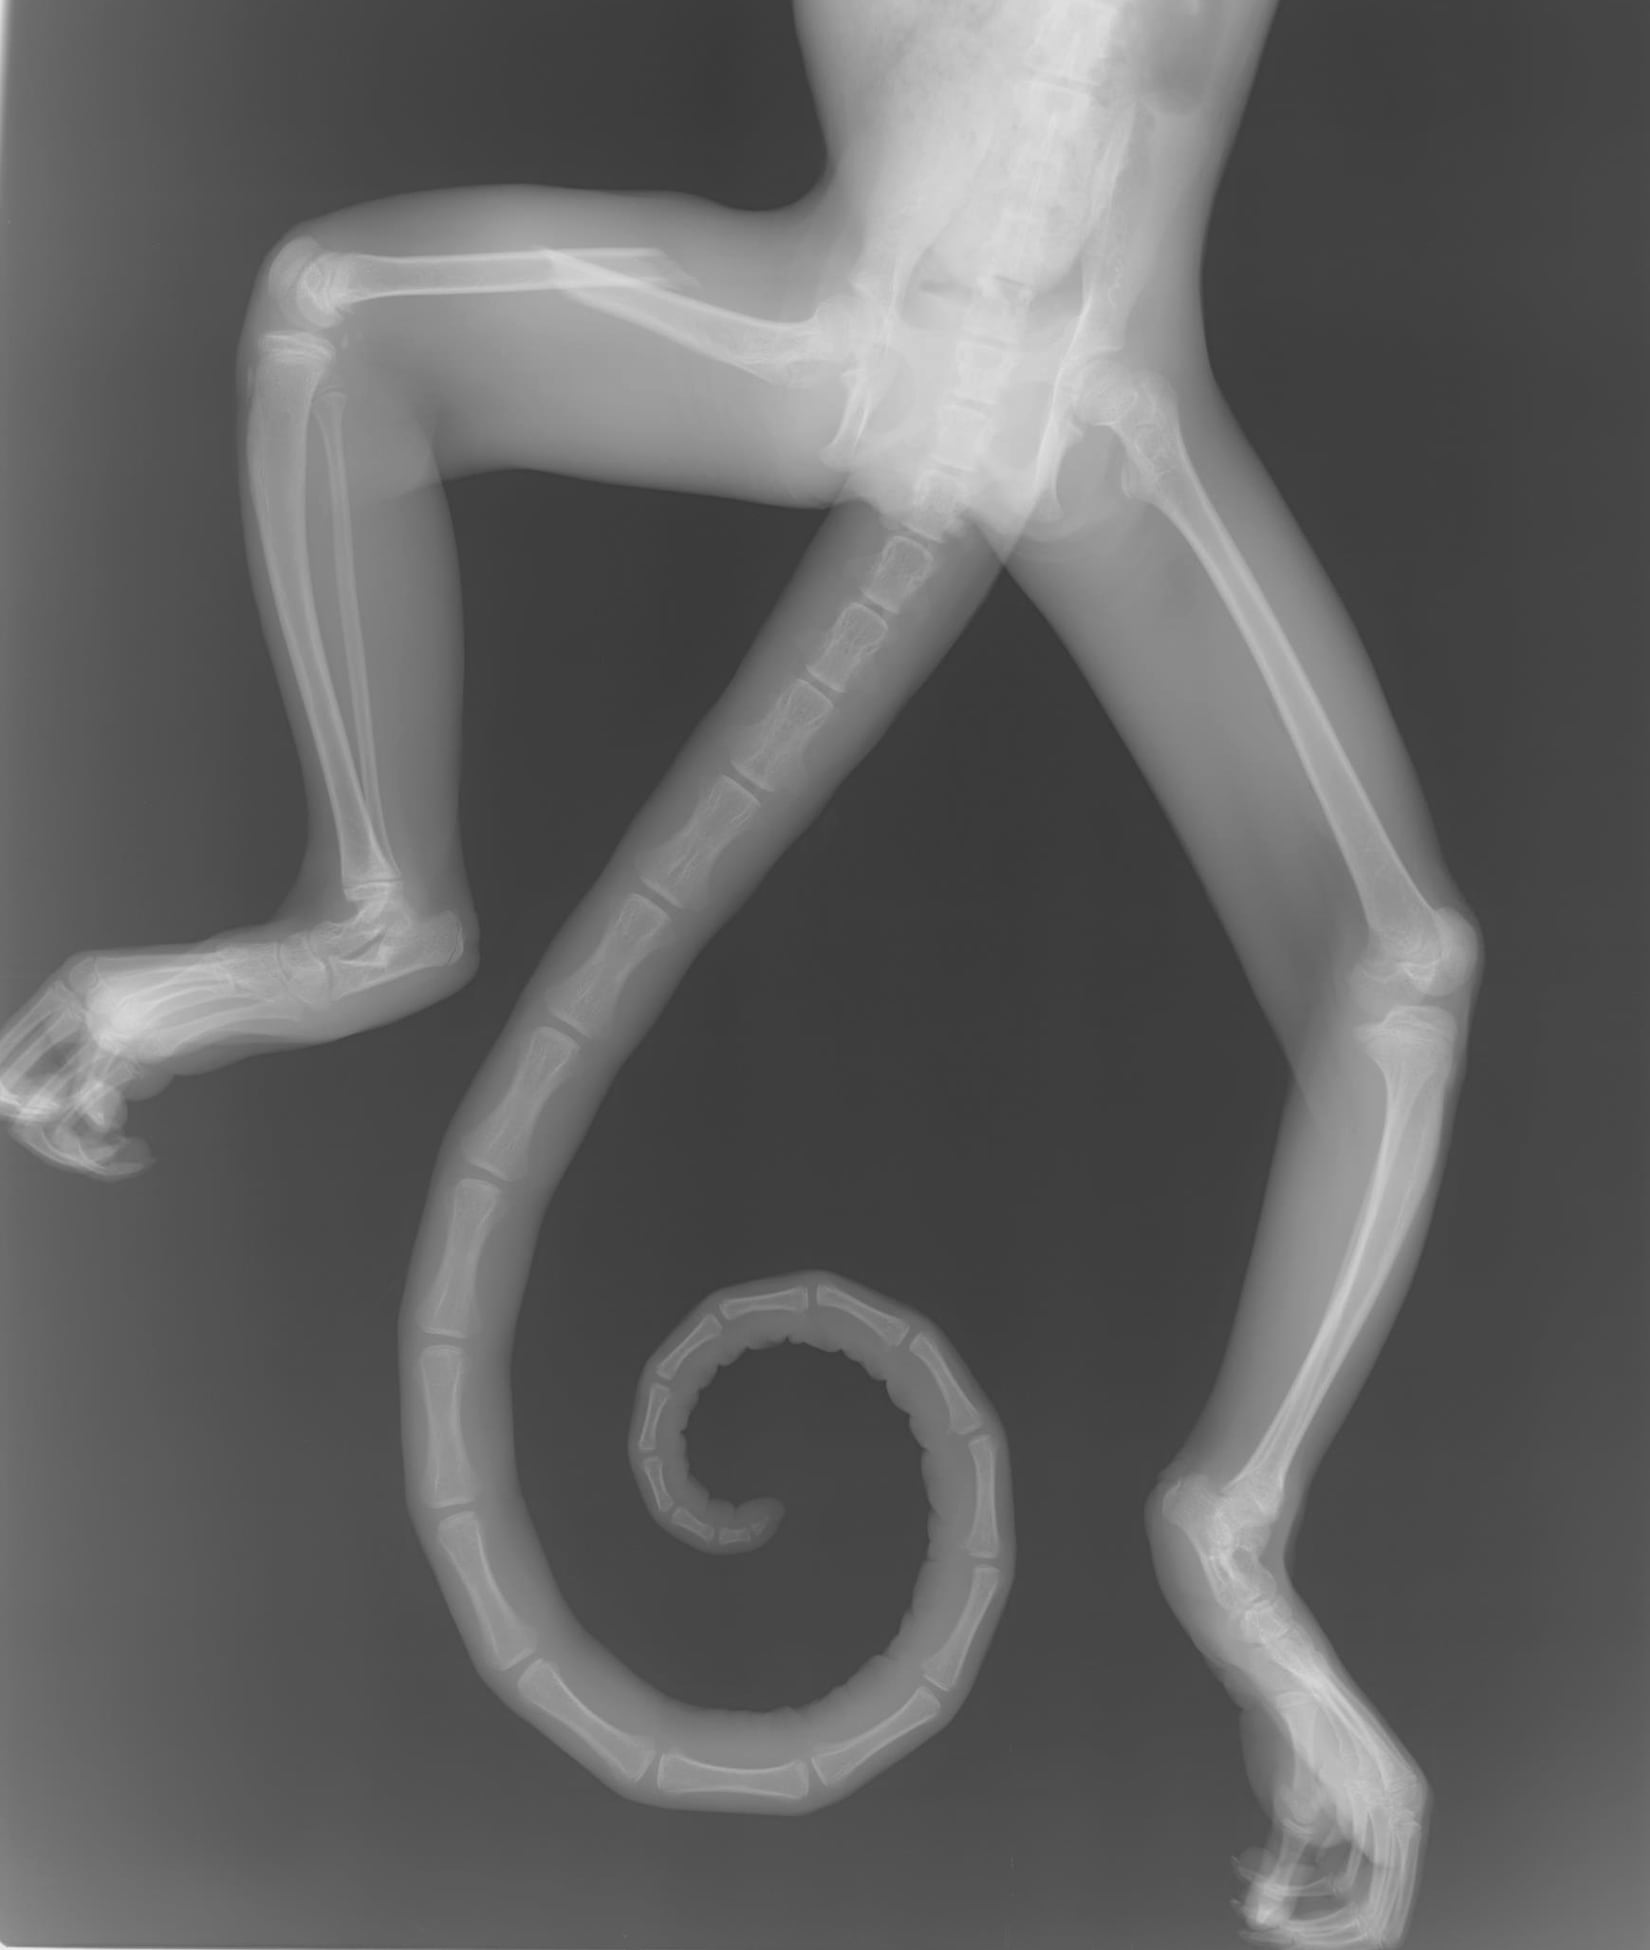

El enfoque de las postales, coloradas en blanco y negro, evitan la crudeza visual, pero no omiten el dolor: evocan el malestar de un pelícano con un anzuelo incrustado en una de sus patas, o uno de los tantos monos fracturados tras caer al asfalto electrocutados.